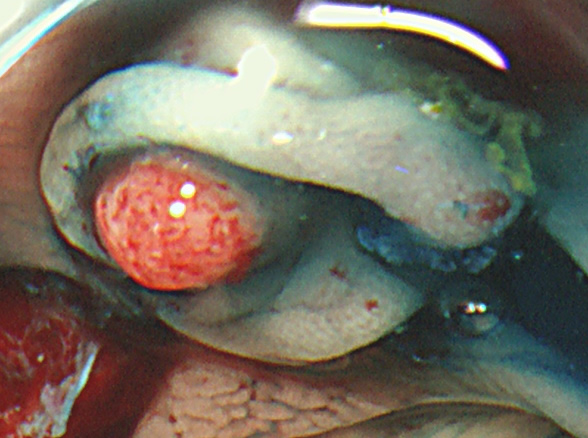

Extended Cold法法で切除された検体は「目玉焼き」のようになります。「黄身」が病変で、「白み」が周囲の正常組織(余白、マージン)です。

腫瘍の取り残しを防ぐために「白み(余白)の大きな目玉焼き」にすることが、最大のポイントです。